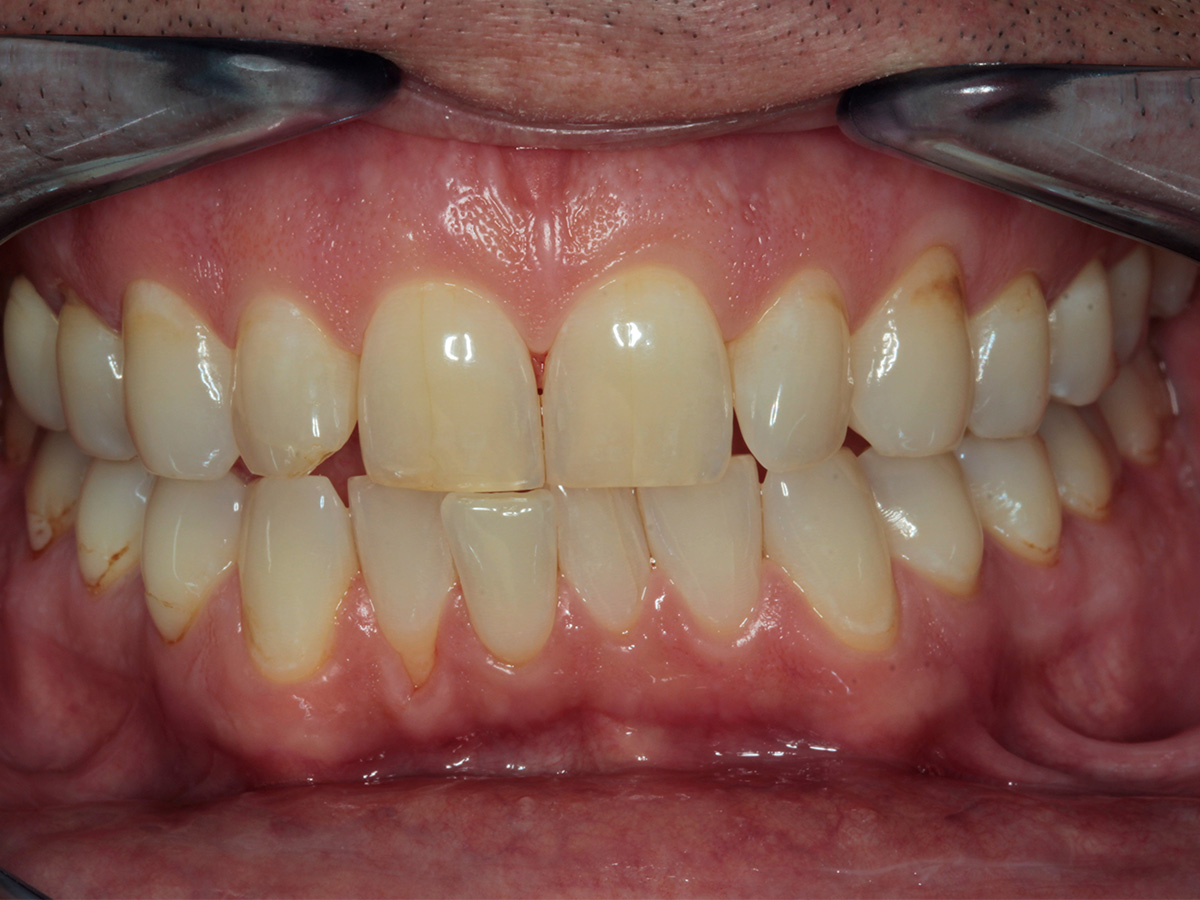

KURSINHALT

In diesem Workshop erhalten Sie umfassendes Wissen für die Behandlung von Parodontitis-Patientenen. Zunächst führt Sie Yvonne Gebhardt durch moderne subgingivale Behandlungskonzepte – das Herzstück der PA-Therapie. Anschließend erklärt Ihnen Sonja Steinert die faszinierenden Zusammenhänge des Knochenstoffwechsels: Wie Entzündungen den Knochenabbau fördern und wie Sie mit gezielter Therapie und Vitamin D gegensteuern können.

• Parodontale Krankheitsbilder erkennen